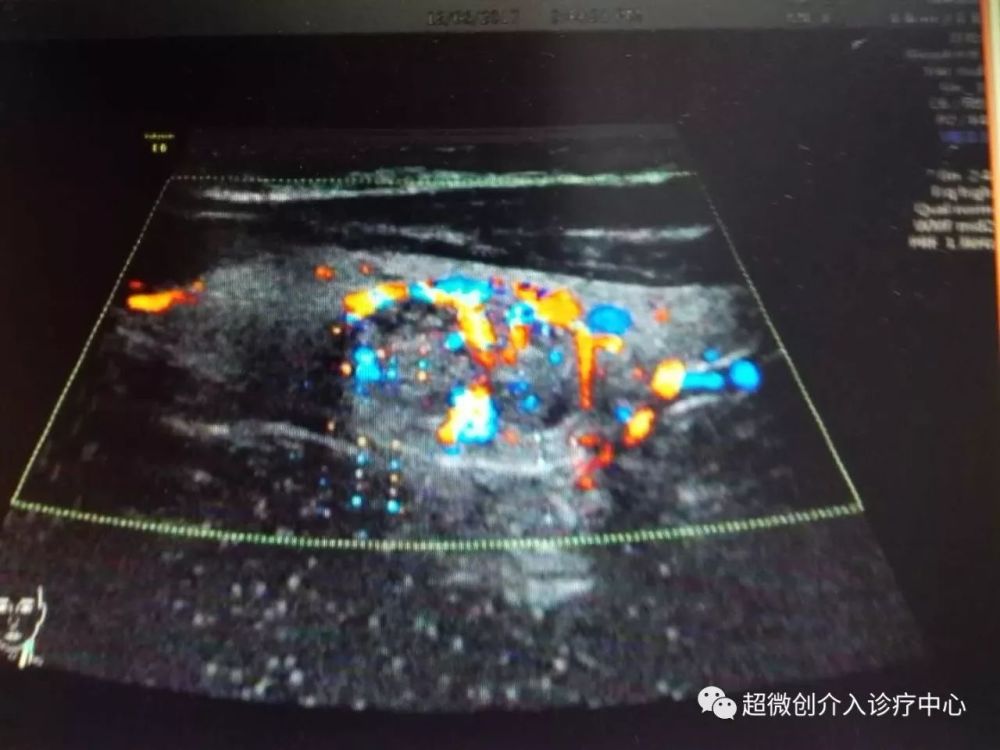

甲状腺结节微波消融术-针尖上的艺术,微创唯美

1280x960 - 101KB - JPEG